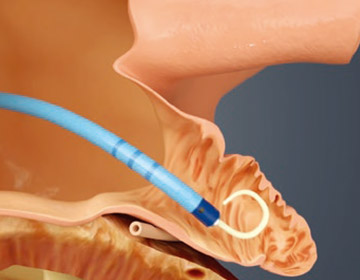

WATCHMANはこのLAAを閉鎖して血栓の形成を防ぎます。手技は経静脈的心房中隔穿刺法であり、カテーテル室において全身麻酔下で実施します。

X線と経食道心エコー(TEE)下で留置手技を実施します。経心房中隔穿刺システムを用いて心房中隔を通過します。

全身麻酔にて手術

手術は原則、全身麻酔、経食道心エコーガイドにて行われます。帰室翌日に歩行可能となります。